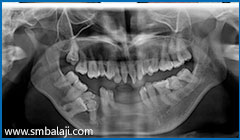

X-ray showing 6 impacted teeth- upper right and left third molars and lower right and left third and second molars